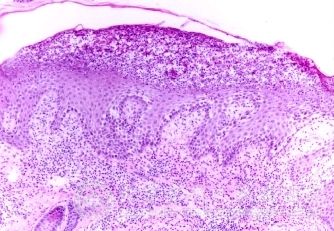

为什么生殖器疱疹可能会引发癌症?目前,有很多人患有生殖器男性疱疹,很多患者问这个生殖器男性疱疹的问题,生殖器男性疱疹给人们的生活工作带来了严重的影响。并且生殖器男性疱疹比较顽固,让人们非常烦恼,生殖器男性疱疹不仅给人们的身体造成了一定的影响,而且生殖器男性疱疹还伴有各种不良症状,为了您能够尽快脱离生殖器男性疱疹,恢复健康,同时避免加重生殖器男性疱疹症状,同时加强对生殖器男性疱疹知识的了解,北京京城皮肤医院就给大家讲解,为什么生殖器疱疹可能会引发癌症?

北京京城皮肤医院指出:由于生殖器疱疹反复发作,难以控制,轻者可导致心脏病、脑膜炎、神经系统损害等疾病,同时生殖器疱疹病毒与生殖器恶性肿瘤关系密切。早在60年代就有人提出引起生殖器疱疹的Ⅱ型疱疹病毒可能是宫颈癌的潜在致癌因子,重者可病变为阴茎癌或宫颈癌。